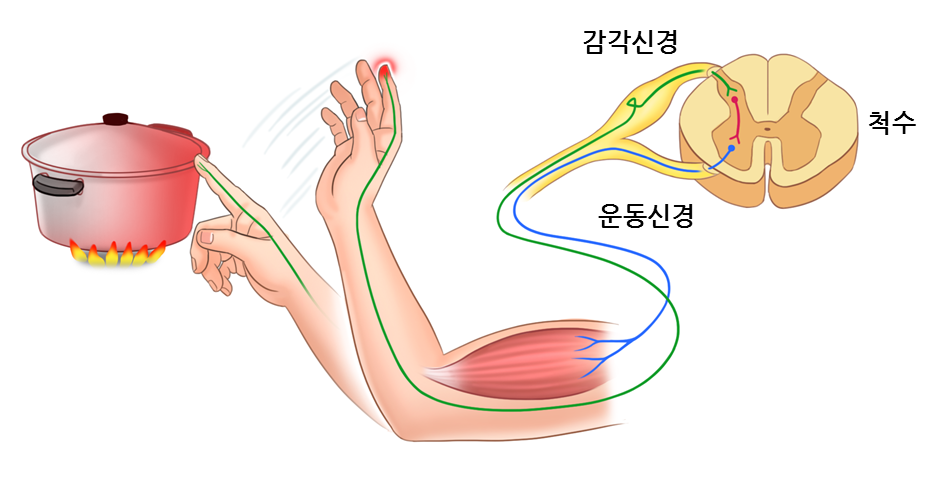

말초 신경에서 감각신경은 척수의 등쪽, 운동신경은 척수의 배쪽에 위치하고 있습니다.

체성신경계는 중추신경계에서 받은 명령을 골격근으로 연결하여 근육운동을 일으키며, 감각기에서 들어온 감각정보를 중추신경으로 전달하여 자극을 느낄 수 있게 해줍니다.